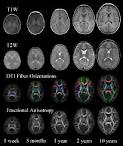

• Η μαγνητική τομογραφία (MRI) με γαδολίνιο (έσω ακουστικών πόρων, οπίσθιου κρανιακού βόθρου, γεφυροπαρεγκεφαλιδικών γωνιών και εγκεφάλου) αποτελεί την πιο ενδεδειγμένη μέθοδο ανίχνευσης ακουστικού νευρινώματος, απομυελινωτικής νόσου και ΑΕΕ, που μπορεί να παρουσιάζονται με πρώτη εκδήλωση την οξεία πτώση ακοής. Η εξέτασηδεν πρέπει να γίνεται άμεσα αλλά τουλάχιατον δέκα ημέρες μετά την πτώση της ακοής.